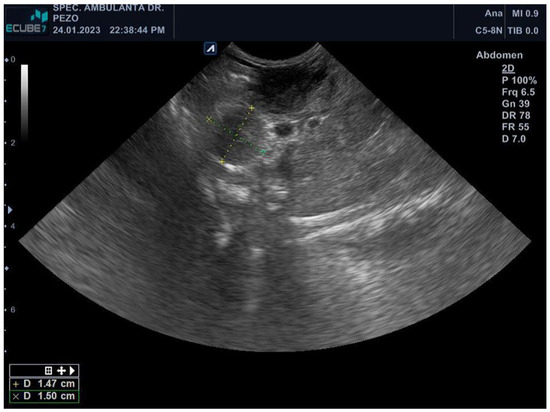

3.2. Diagnostics